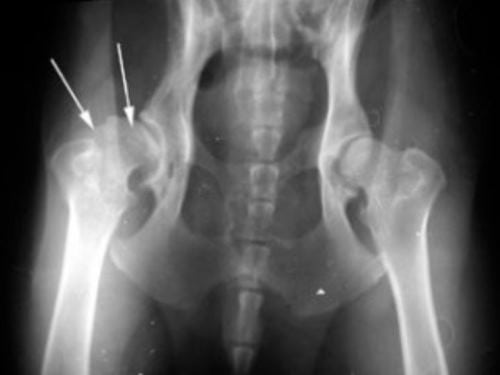

| Вторая | Боли становятся интенсивнее, беспокоят человека даже в состоянии покоя, распространяются в пах и бедра. А после подъема тяжестей больной заметно прихрамывает. Наблюдается ограничение отведения ноги и ее внутренней ротации. На рентгенографических снимках хорошо заметны неравномерное сужение суставной щели, деформация и смещение бедренной головки, формирование большого количества остеофитов (костных наростов) |

| Третья | Человек постоянно ощущает боль в области бедра, которая возникает даже в ночные часы. При ходьбе используется трость, объем движений резко снижается из-за атрофии ягодичных и бедренных мышц. Укорочение конечности приводит к изменению положения тела, что еще больше нагружает пораженный болезнью сустав. На рентгенографических изображениях наблюдается полное или частичное сращение суставной щели |

Диагноз выставляется на основании жалоб пациентов, внешнего осмотра, результатов тестирования, определяющих объем движений в тазобедренном суставе. Наиболее информативна рентгенография.